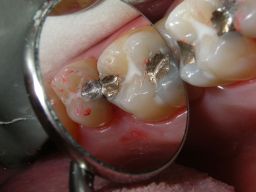

Warum ist das wichtig? Nun, Amalgam ist nicht gleich Amalgam. Es gibt, wie auch bei Composites, gravierende Qualitätsunterschiede schon im Material, die voll auf die Haltbarkeit der Füllungen durchschlagen. In einer Meta-Analyse haben sich Gamma-2-freie Amalgame mit Zink als besonders haltbar gezeigt - nach 13 Jahren waren noch 85 von 100 Füllungen im Mund. "Epoque 70" ist solch ein Amalgam und enthält darüberhinaus 70% Silber im Metallpulver. Dadurch bleibt es auch langfristig silbrig-hell, die Füllungen werden nicht schwarz. Die Bilder sind anklickbar! | ||||||||||||||||||||||||||||||||||||||||||||||||||||||||||||||||||||||||

![]() | Die Füllungen links wären auch in Composite gut vertretbar gewesen, die Füllungen rechts halten in Amalgam sicher länger als in Composite. Diese Amalgamfüllungen sind alle im Oberkiefer und im Alltag nicht sichtbar. |